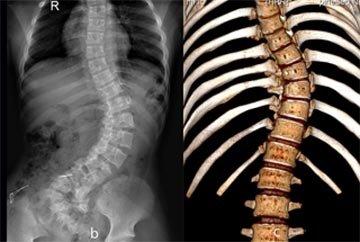

正常脊柱从背后看是直的,侧面看是呈S型的。脊柱侧弯在触摸脊柱时,常可发现脊柱异常弯曲或后凸,肩胛和背部不对称,高低不平。脊柱侧弯都有哪些症状呢?>>我的这些症状是脊柱侧弯吗?请在线医生帮忙判断!

严重的病人,外观特别明显,根据不同的侧弯类型和部位(颈段、胸段、胸腰段、腰段)可以出现一个肩膀高,一个肩膀低,身体向一侧偏斜,骨盆也一边高一边低、不平衡,下肢不等长等现象,尤其是能明显看到胸背部某处突出一大块,而另一处则有一大凹陷存在,前胸也不平整,两边明显不对称。当侧弯进一步发展超过100度以后,压迫脊髓神经,部分患者还可出现神经症状,轻者下肢麻木、无力、肌肉萎缩;重者可能出现截瘫。>>脊柱侧弯危害这么大,用什么办法治疗效果较好?